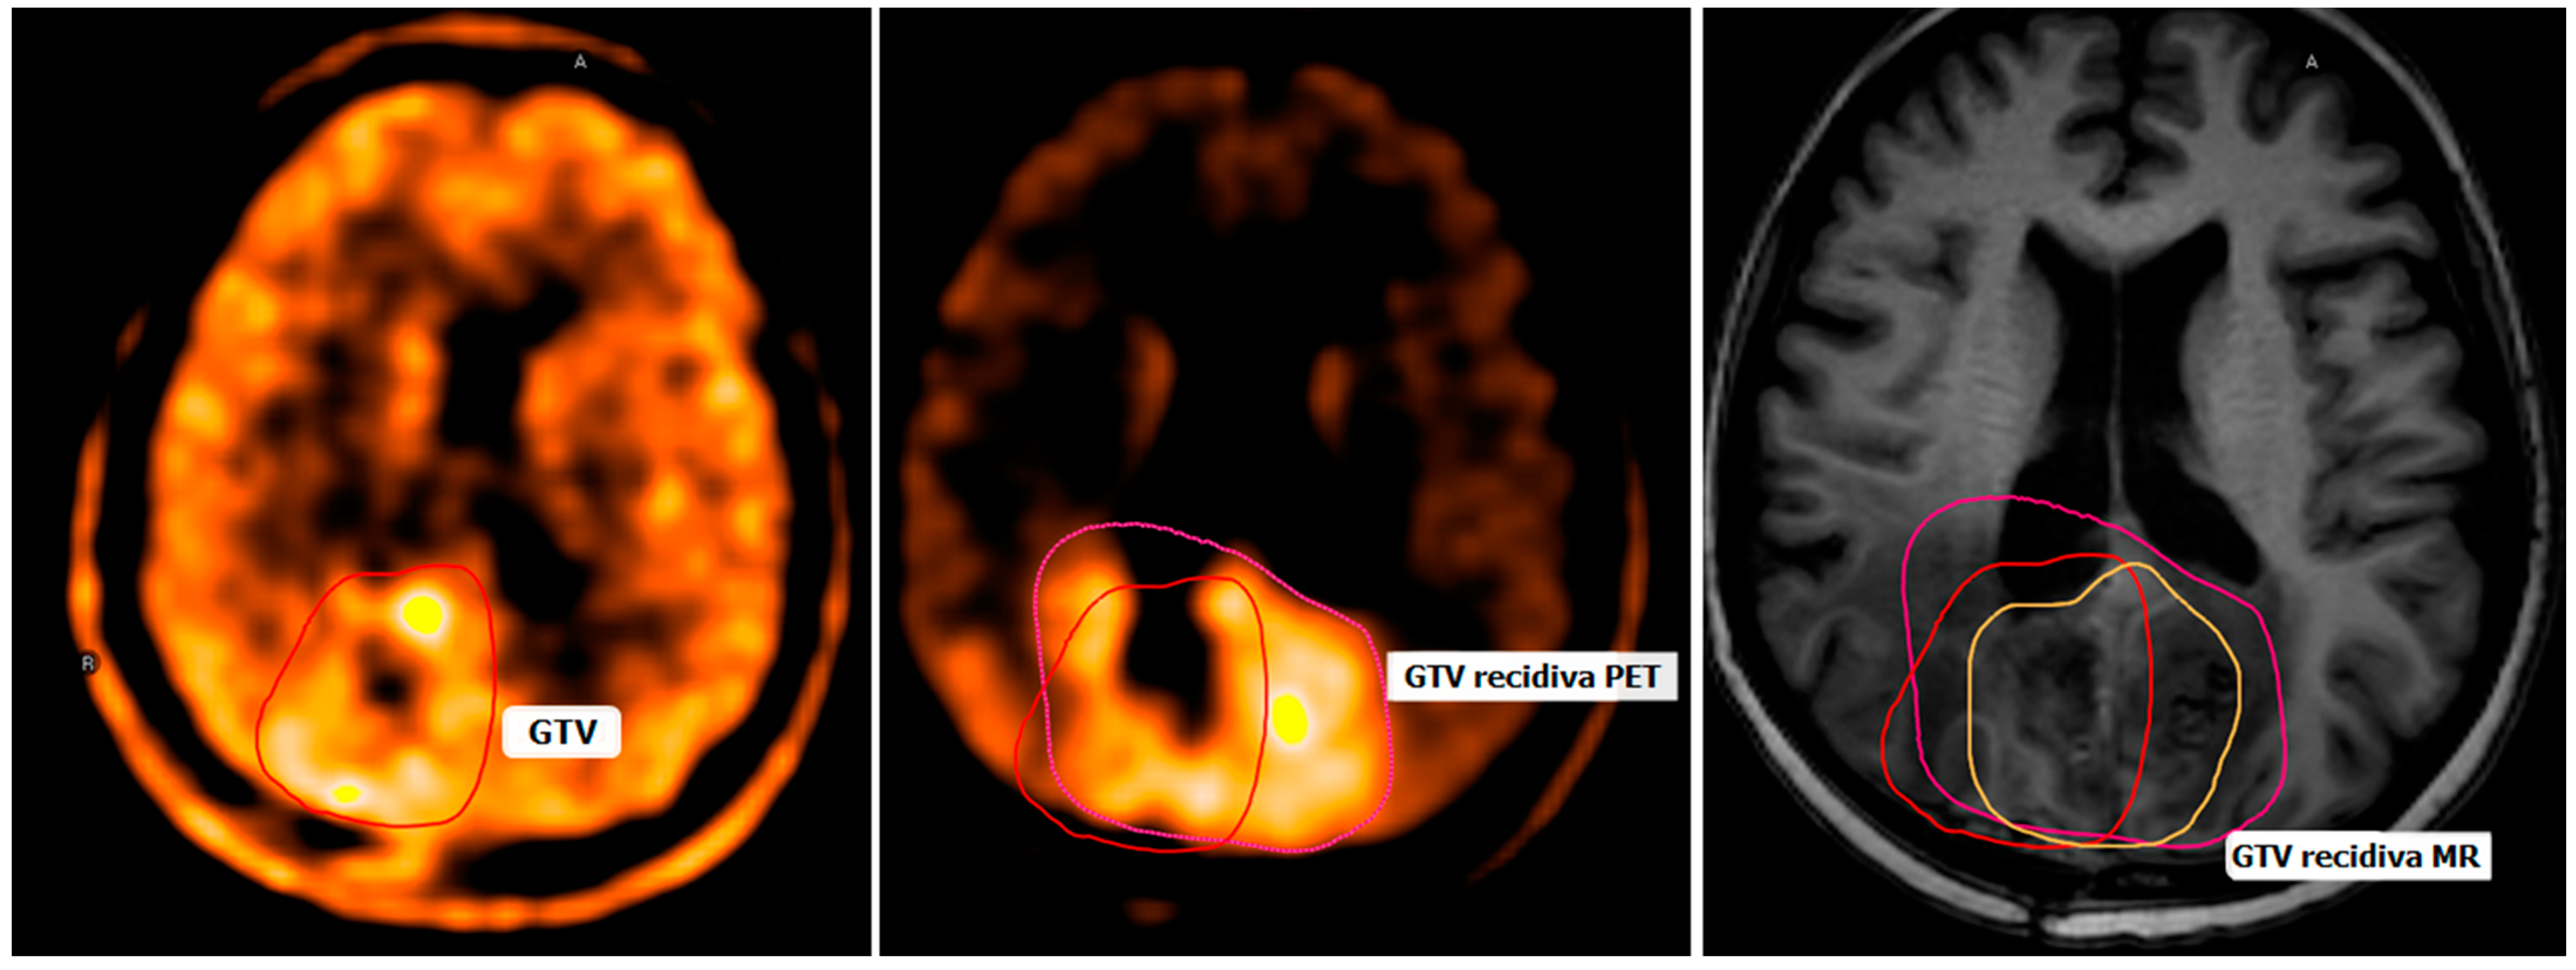

- Debreczeni-Máté, Z.; Törő, I.; Simon, M.; Gál, K.; Barabás, M.; Sipos, D.; Kovács, A. Recurrence Patterns after Radiotherapy for Glioblastoma with [(11)C]methionine Positron Emission Tomography-Guided Irradiation for Target Volume Optimization. Diagnostics 2024, 14, 964. [Google Scholar] [CrossRef] [PubMed] [PubMed Central]